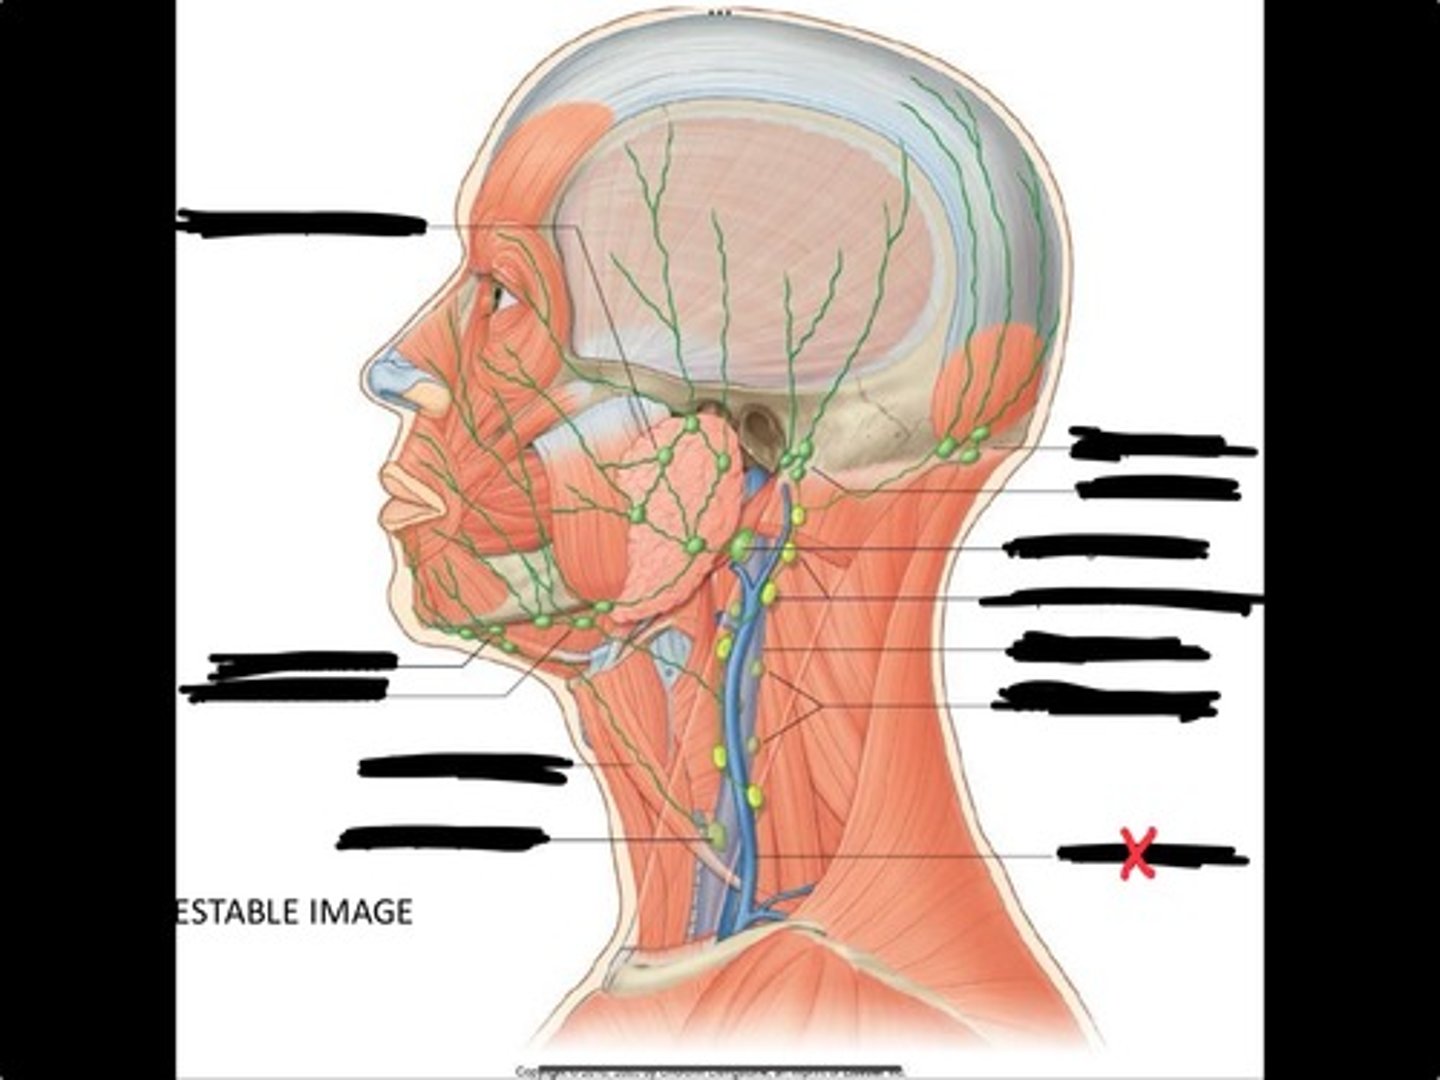

Jugulo-omohyoid node

Omohyoid muscle

Submandibular nodes

Submental nodes

Pre-articular/parotid nodes

Occipital nodes

Mastoid nodes

Jugulodigastric nodes

Superficial cervical nodes

Internal jugular vein

Deep cervical nodes

External jugular vein